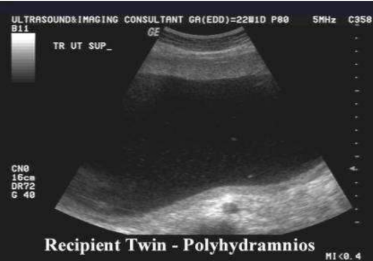

polyhydraminos

too much fluid

polyhydraminos is assoc with

TTTS

AFI of oligohydramnios

AFI of polyhydramnios

more than 24cm

largest single pocket more than 8cm